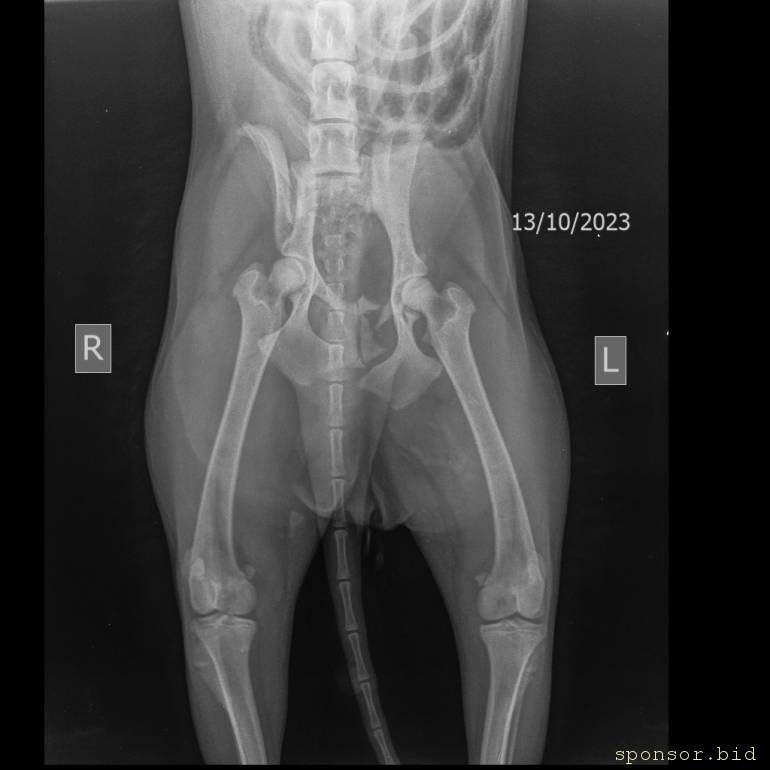

На втором снимке видно как раздроблена кость

Мою собаку сбила машина - Скелет средний 10-25 kg-Тазовые кости VD-13.10.2023-15_31_39-169.JPEG